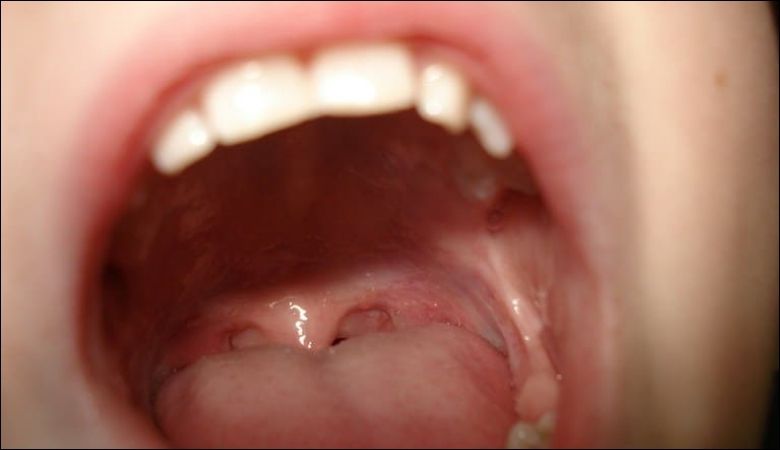

Nhiễm virus như HPV hoặc vi khuẩn liên cầu khuẩn có thể gây ra các nốt sần ở cuống lưỡi

Nhiễm virus như HPV hoặc vi khuẩn liên cầu khuẩn có thể gây ra các nốt sần ở cuống lưỡi, kèm theo đau họng. Theo WebMD, các nhiễm trùng này thường đi kèm với sốt hoặc sưng amidan.

Nếu nghi ngờ nhiễm trùng, cần thăm khám bác sĩ để được xét nghiệm và điều trị phù hợp. Nha khoa Parkway cung cấp dịch vụ kiểm tra để xác định nguyên nhân viêm nhiễm.